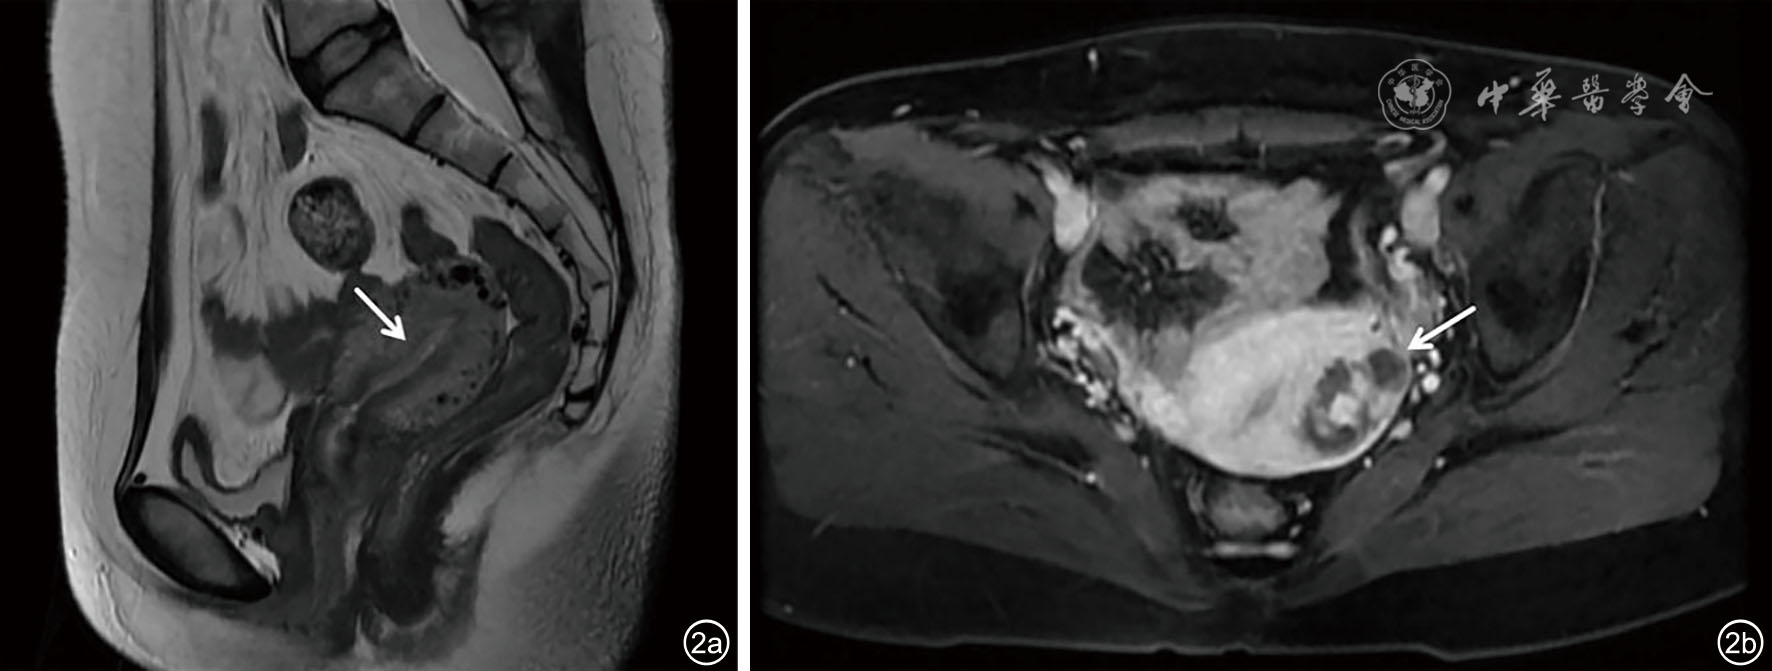

图2 肌壁间异位葡萄胎妊娠盆腔增强MRI图像。图a为矢状位显示宫腔线清晰,结合带完整,未见异常信号;图b为增强轴位示宫底偏左肌层内混杂信号团块,血供丰富